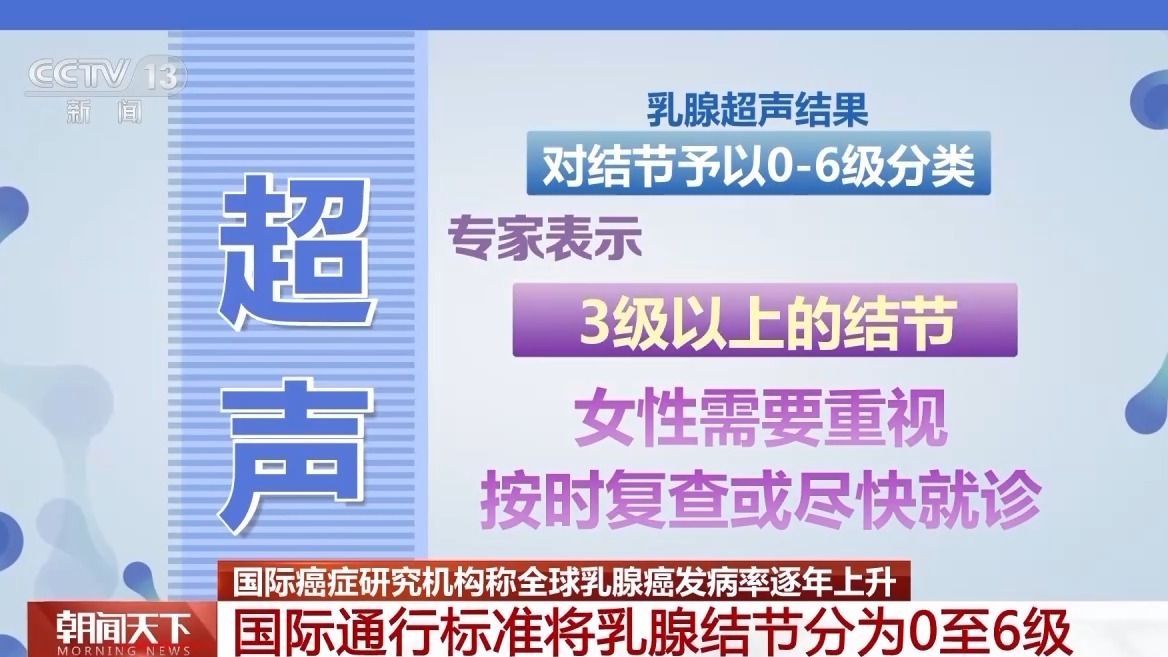

凭据海外通行的BI-RADS分级步地,对结节给以0至6级分类。大师示意,3级以上的结节,女性需要深爱,按期复查或尽快就诊。

北京大学肿瘤病院乳腺癌珍重疗养中心副主任大夫 霍苓:3级,一般半年要进行重叠的超声查验;4级相对来讲恶性风险跨度相比大,一般提倡要穿刺活检;5级的话即是高度怀疑恶性,是以一定要穿刺明确会诊,进行后续的疗养;6级即是仍是在其他所在穿刺确诊为乳腺癌的病灶。